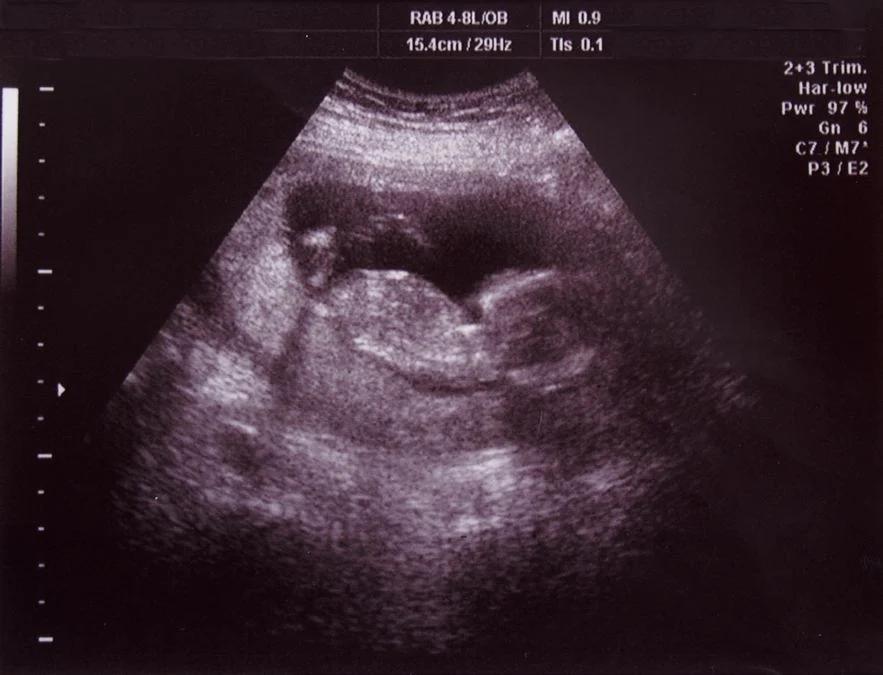

Wie wird die NT-Messung durchgeführt?

Die NT-Messung wird während einer routinemäßigen Ultraschalluntersuchung durchgeführt. Der Arzt oder die Ärztin verwendet einen Ultraschallkopf, um Bilder des Babys im Mutterleib zu erzeugen. Die Nackenfalte wird an der breitesten Stelle gemessen. Die Messung selbst dauert nur wenige Sekunden.